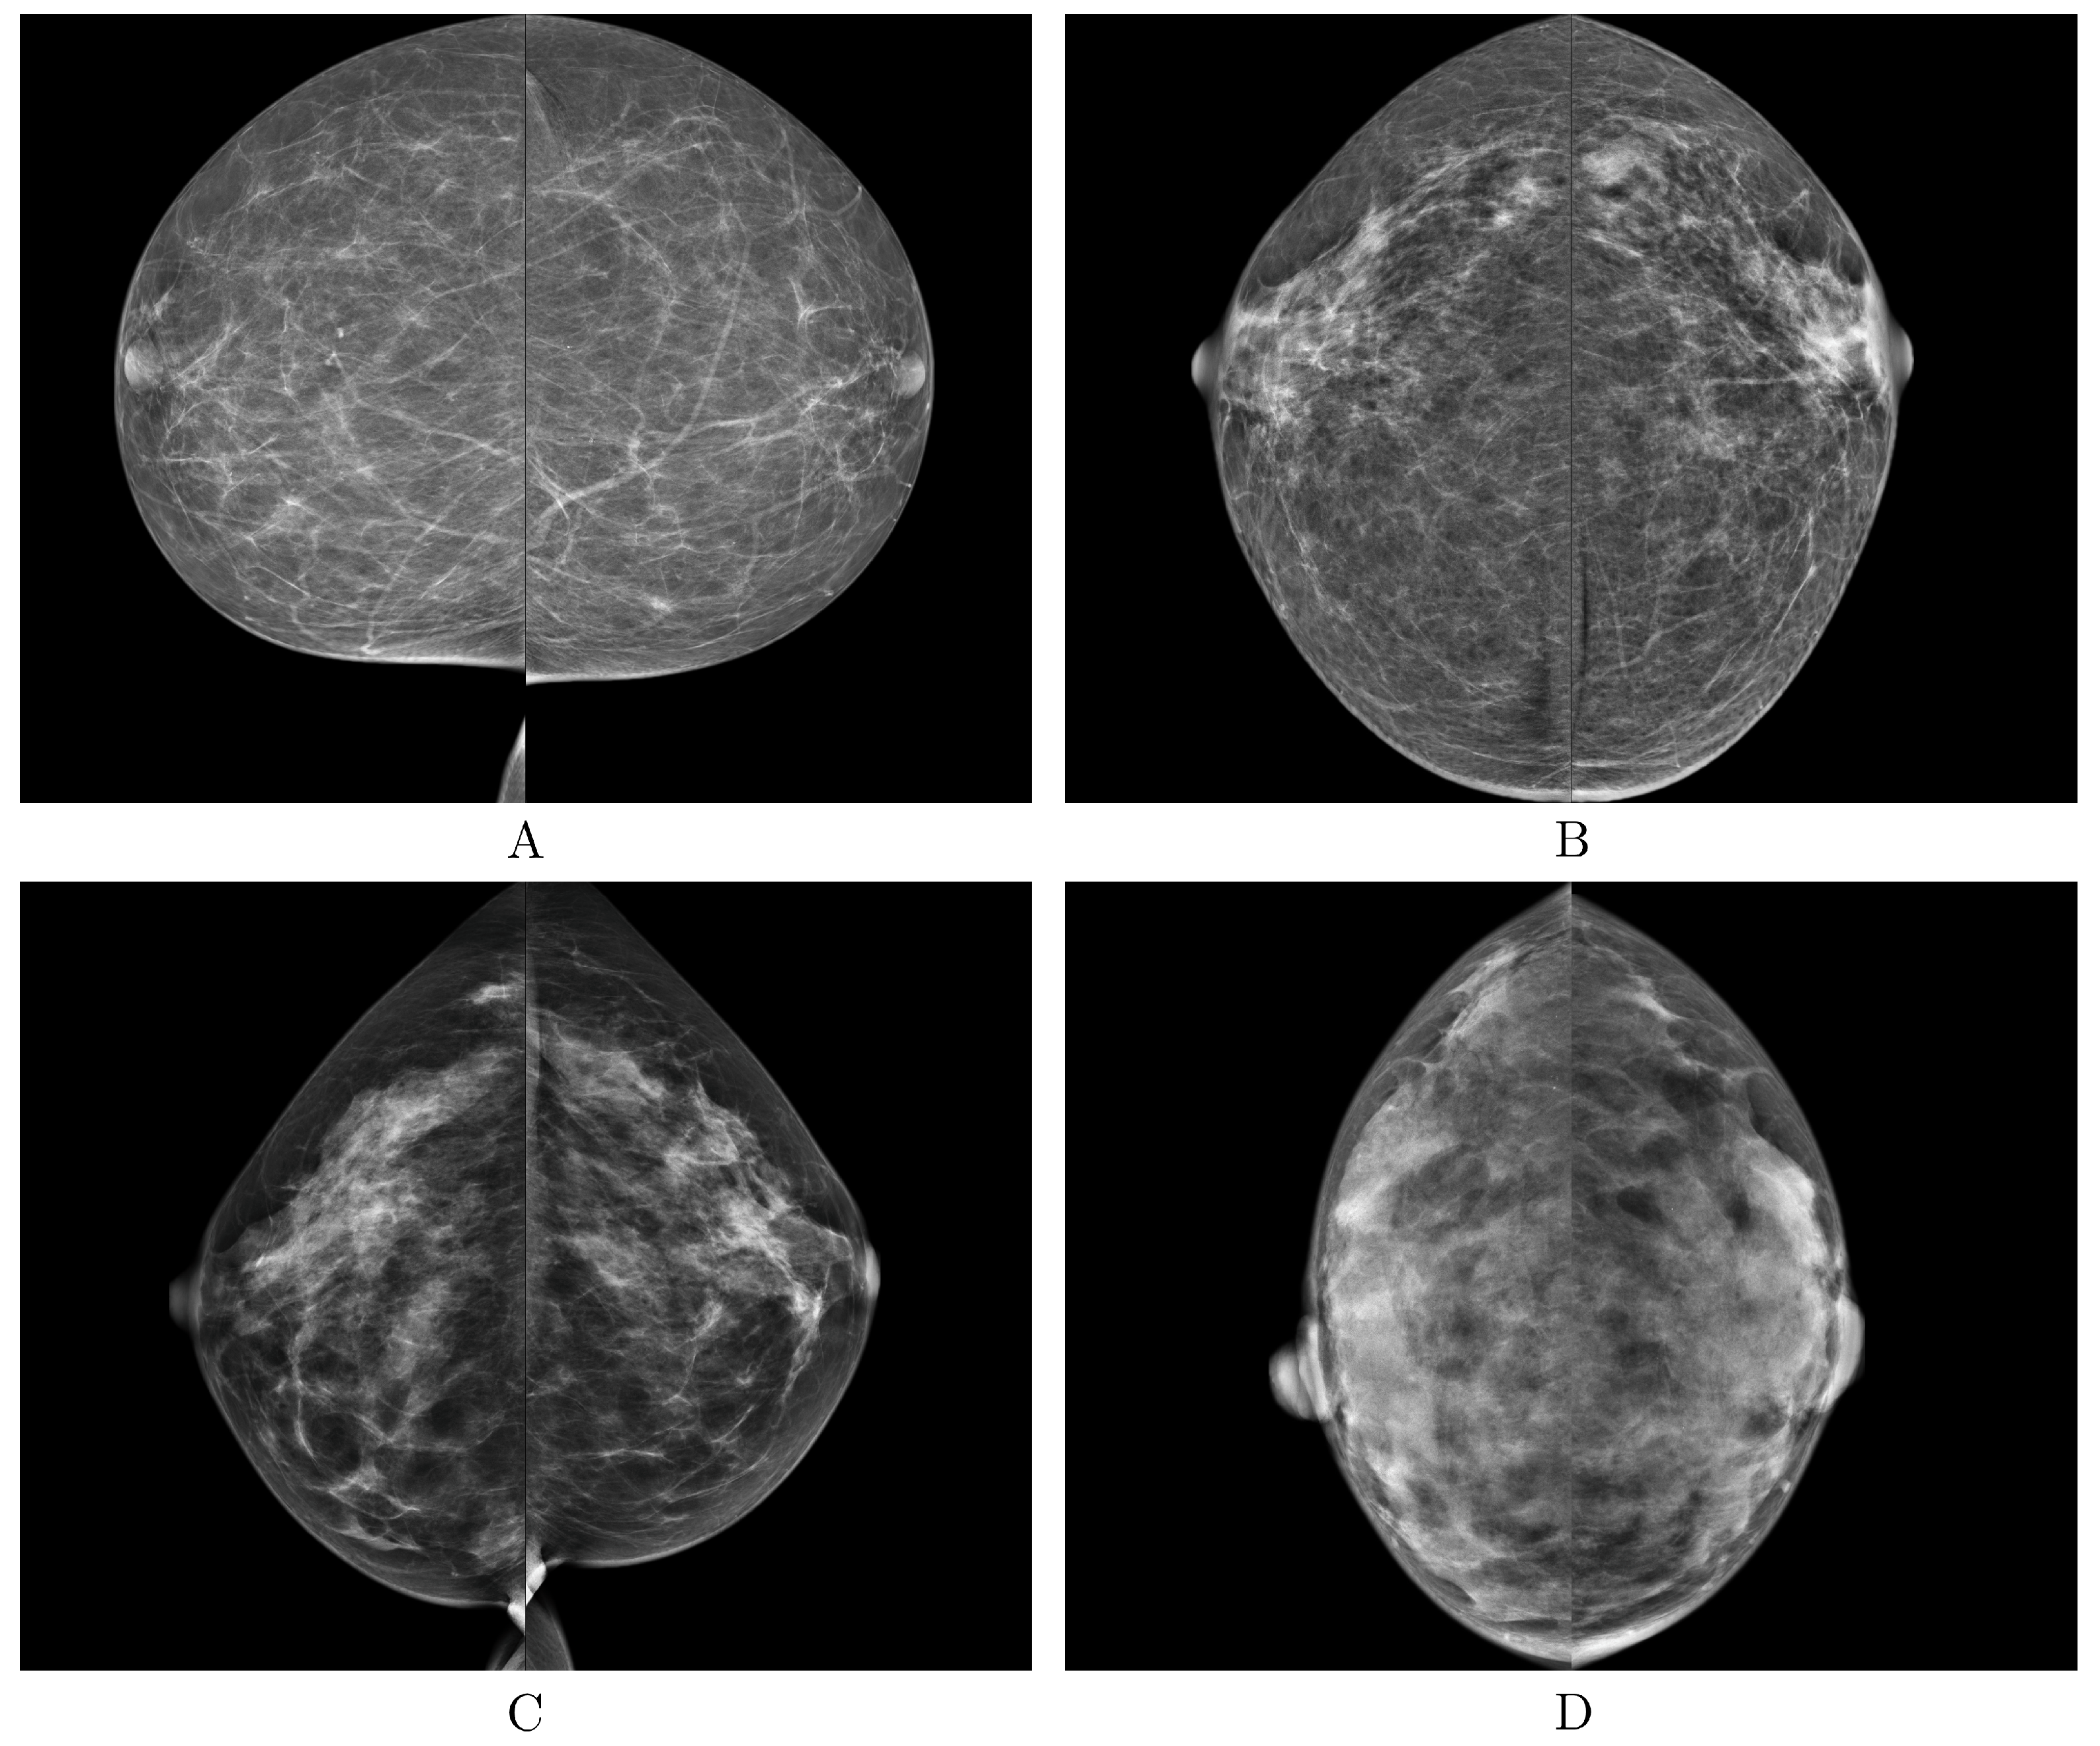

| BI-RADS | Breast Imaging-Reporting and Data System |

| BI-RADS Category | / |

|---|---|

| Class A | 879/3516 |

| Class B | 3212/12,848 |

| Class C | 928/3712 |

| Class D | 111/444 |

| Total | 5130/20,520 |